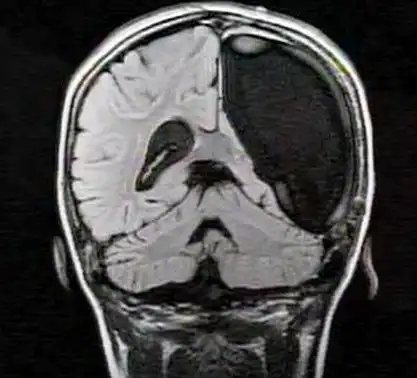

Совершенное зрение 10-летней немецкой девочки поставило в тупик врачей, поскольку она родилась только с левым полушарием головного мозга. Для хорошего зрения необходимо наличие обоих полушарий, потому что визуальная информация, поступающая от зрительных нервов, передается в противоположное полушарие для переработки и хранения там. Так, наличие лишь одного полушария должно свидетельствовать о том, что должен работать лишь один глаз, в случае с девочкой, только правый.

Тем не менее, девочка отлично видит, и наслаждается нормальным, бинокулярным зрением, а в 2010 году врачи отсканировали ее мозг, чтобы понять причину происходящего. Оказалось, что посредством процесса, известного, как пластичность, зрительный нерв из левого глаза мигрировал в ее левое полушарие, другими словами, левая часть мозга девочки принимает визуальную информацию от обоих глаз.

Поразительно, в зрительной коре ее левого полушария сформировались специальные районы, предназначенные для обработки информации, получаемой левым глазом. Это помогает избежать путаницы.